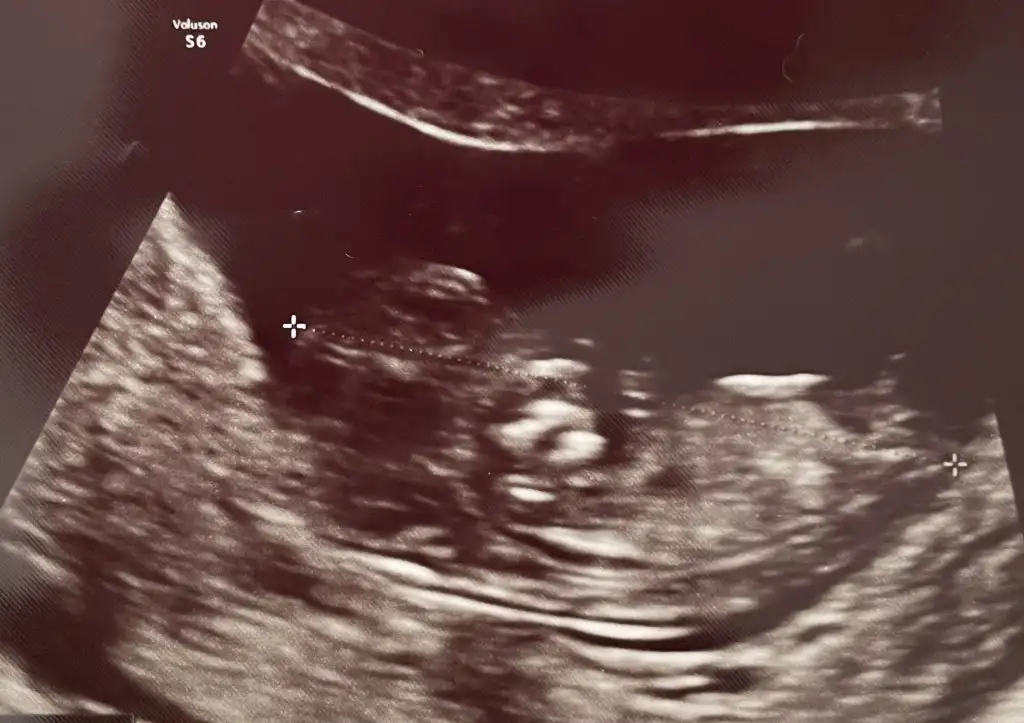

IMG_7092.webp

sırtı dönük ama